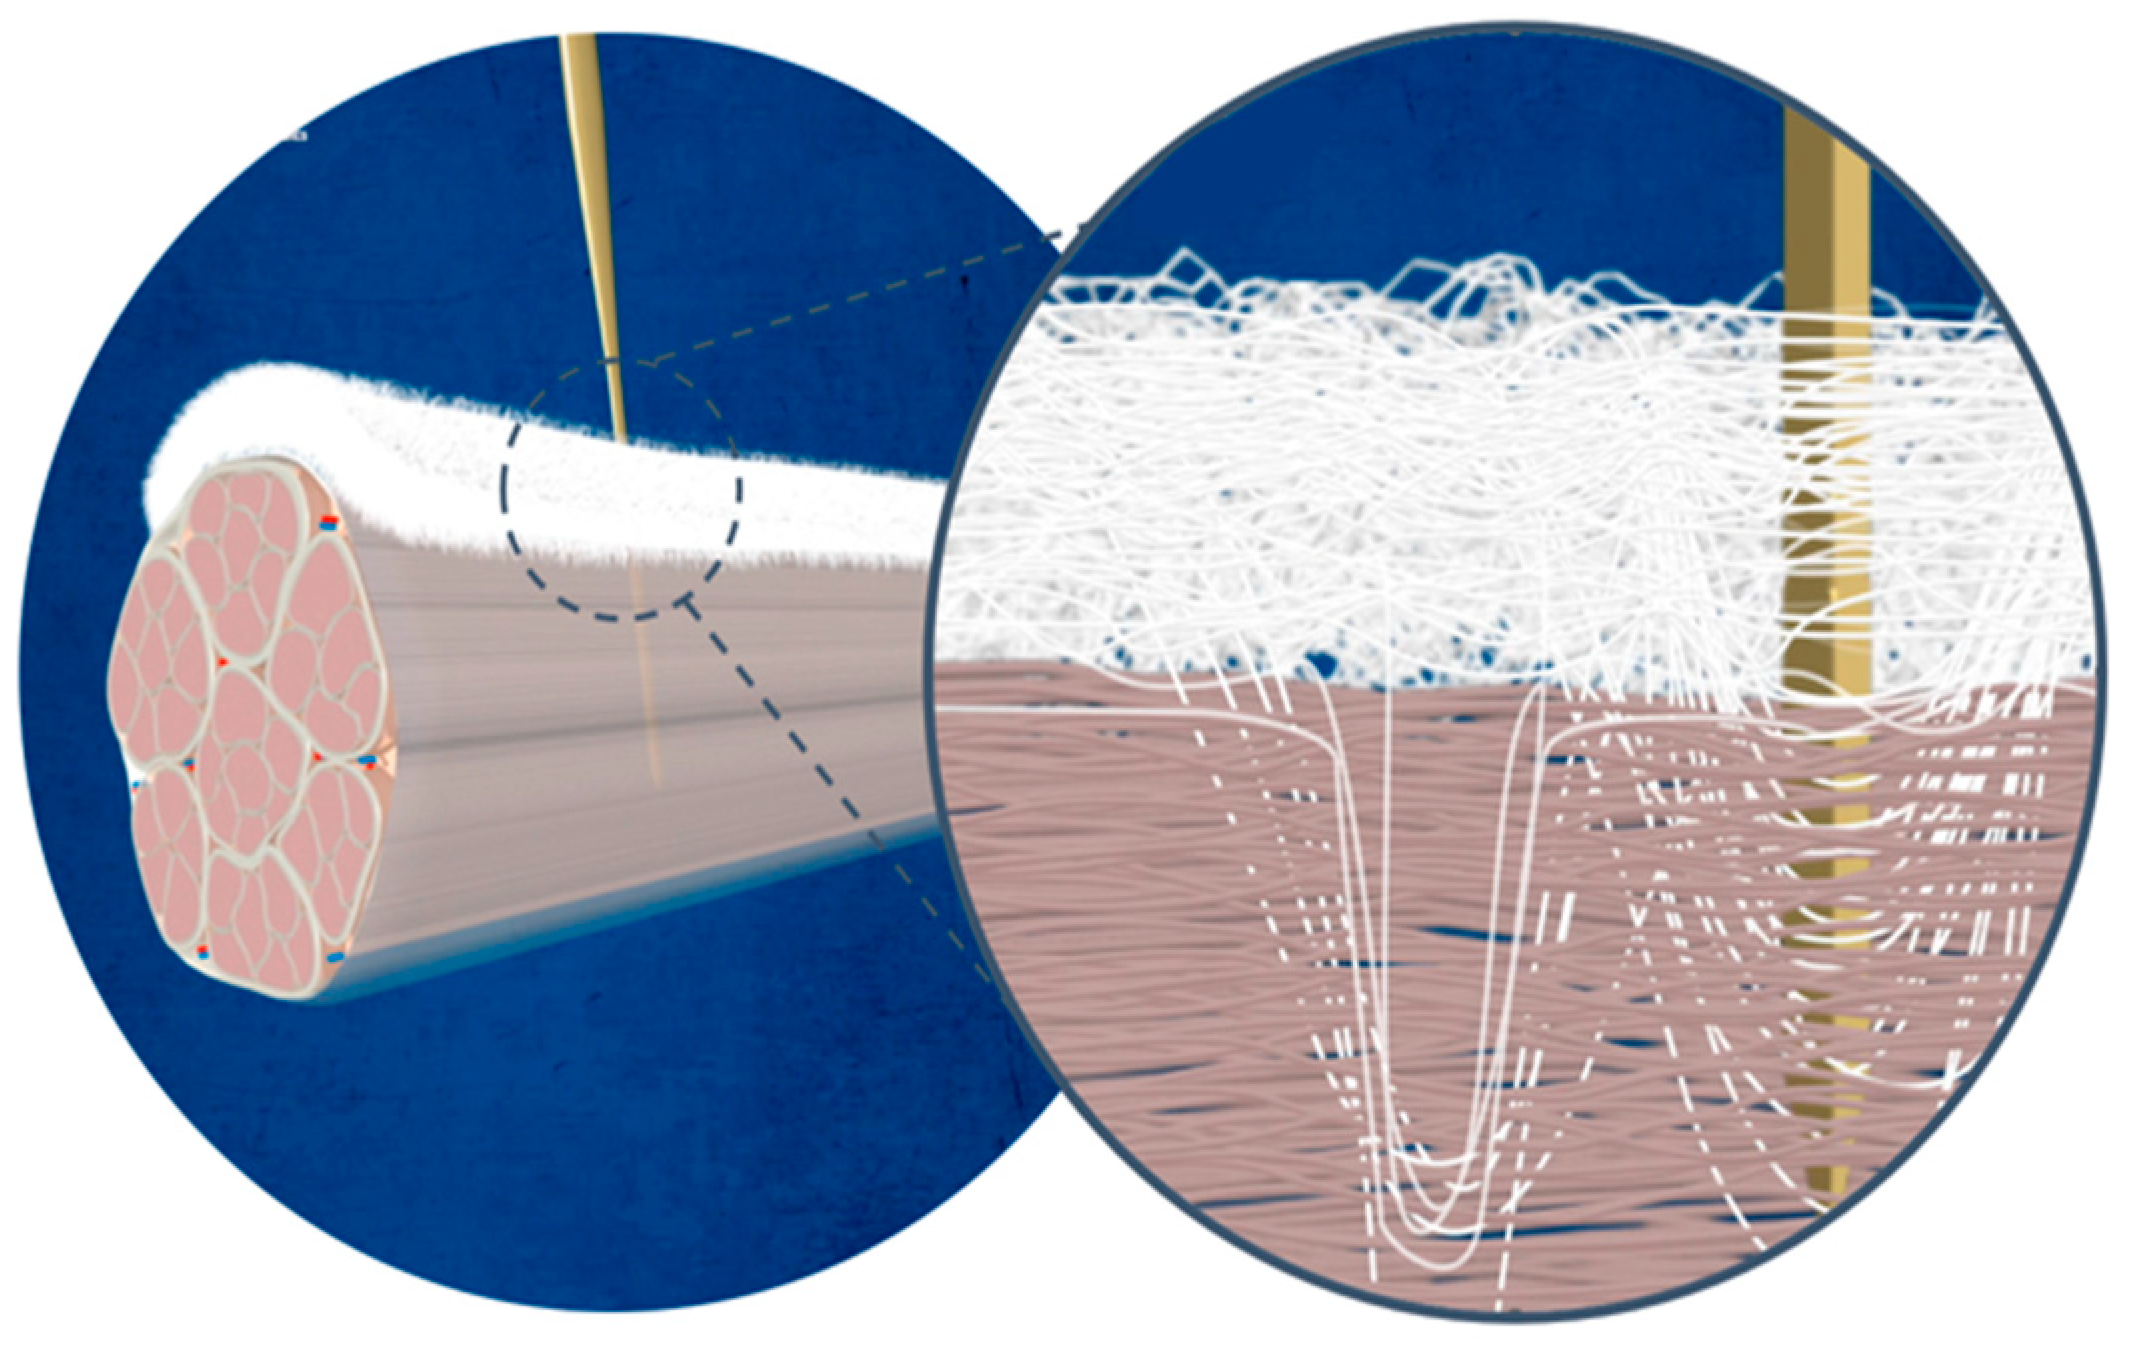

3.1.4. The Future of Patch Augmentation

3.1.6. Bioresorbable Scaffolds

3.3.1. Mesenchymal Stem Cells (MSCs)